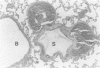

The effects of disturbances of the pulmonary circulation on the formation of pulmonary emphysematous bullae in rabbits were studied with the use of changes in the parenchyma of lungs insulted by both pulmonary embolization with Sephadex beads and carrageenan-induced pneumonia. Rabbits given one of the larger doses of Sephadex and then carrageenan in solution had giant bullous lesions in the lobe treated with those agents 2 months later. More animals had bullous lesions in the groups given the larger doses of Sephadex than in groups given the smallest dose or none. In animals killed after 2 weeks, bullous lesions were found, whereas there were none in those killed after 1 week. These results suggest that the size and number of bullous lesions forming in the treated lobes are associated with the dose of Sephadex. Giant and small bullous lesions are varieties of the same disorder, and there seems to be a latent period for development.